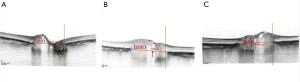

Advancements of OCT with enhanced depth imaging (EDI) allows a high-resolution visualisation of the deep optic nerve including lamina cribrosa (LC), Bruch membrane opening (BMO), as well as prelaminar tissue and laminar depth (19). Our previous observation has shown that the optic nerve head in glaucoma patients is characterized by LC thinning, in contrast with NAION eyes (22). Another study reported prelaminar tissue thickening and BMO enlargement in the acute oedematous NAION eyes compared with unaffected eyes; these changes actually reversed over time (23). EDI OCT also was employed to show detailed optic nerve head crowding in NAION, which is considered the main risk factor for the development of NAION. OCT also has changed our understanding of the possible role of the size of the scleral canal in the development of NAION. Studies using confocal scanning laser ophthalmoscopy (Heidelberg Retina Tomograph II, Heidelberg Engineering GmbH, Dossenheim, Germany) suggested that NAION eyes had smaller optic disc diameter and area as compared to control eyes (8). Subsequently, Hayreh et al. (24) hypothesized that the BMO in patients with “discs at risk” for NAION was smaller than in the general population, resulting in the characteristic optic disc crowding. However, direct comparison between clinical optic disc/fundus examination and SD-OCT imaging of the optic nerve head is inappropriate, as the information derived from each method is distinct and not comparable (25). We measured BMO area with EDI OCT in post-acute NAION and their fellow eyes and compared these measurements with normal eyes. Of note, BMO area was similar in three groups (26). Similarly, several time-domain OCT studies also have shown that BMO is not smaller in patients with NAION than in age-matched controls (6,27). Another EDI OCT study also determined that BMO area in NAION and control subjects was not significantly different (28). We also measured prelaminar tissue (perpendicular distance between the internal limiting membrane (ILM) surface and anterior laminar surface) in post-acute NAION eyes. We found prelaminar tissue thickening in both NAION eyes and unaffected fellow eyes of NAION patients, as compared to eyes in normal control subjects. Given that we identified thickened prelaminar structures in both the affected and unaffected eyes of patients with NAION (Figure 2), we suggest that this change might be pathogenic and not a consequence of the disease (26). Another study also found thicker (but not significant) prelaminar tissue in NAION fellow eyes compared to controls (29). Further and even more importantly, though, EDI OCT allowed us to measure peripapillary choroidal thickness. Our group has found a thicker peripapillary choroidal structure in both the affected and unaffected fellow eyes of NAION subjects when compared to control subject eyes (30). Studies by Pérez-Sarriegui et al. (31), and Nagia et al. (28) confirmed our results in finding a bilaterally thicker choroid in patients with NAION. It seems that apparent thick prelaminar neural tissues have been pushed anteriorly by a thickened peripapillary choroid, and both features contribute to the appearance of a “crowded” disc in NAION.

Several studies have reported findings of peripapillary OCT-A in eyes following NAION both in acute and post-acute stages. Both a reduced RPC density in acute NAION and a progressive vessel reduction within 3 months, which correlates with GCIPL thinning, have been shown (41,42). Wright Mayes et al. (43) also showed flow impairment in the RPC corresponding to structural OCT deficits of the RNFL in 80% of eyes. In eyes with optic disc swelling we employed customized image analysis with major vessel removal to measure peripapillary capillary density (PCD). We showed lower PCD in eyes with disc swelling due to NAION compared with papilledema (Figure 3) (44).